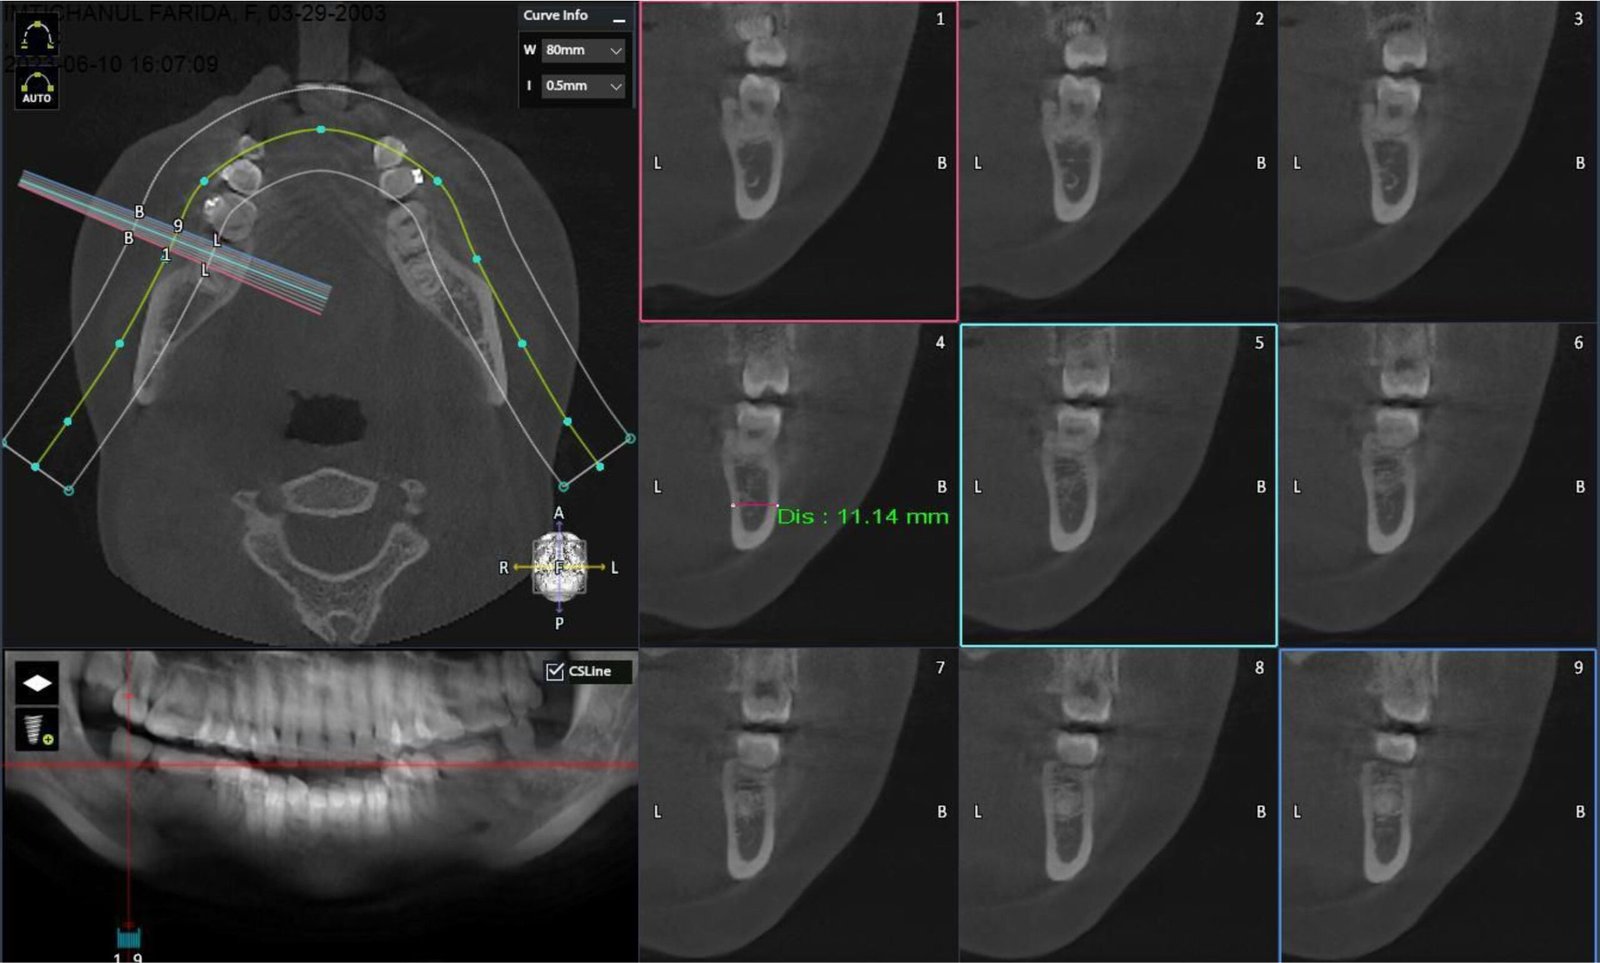

Rontgen CBCT adalah rontgen beresolusi tinggi yang menghasilkan gambar 3 dimensi